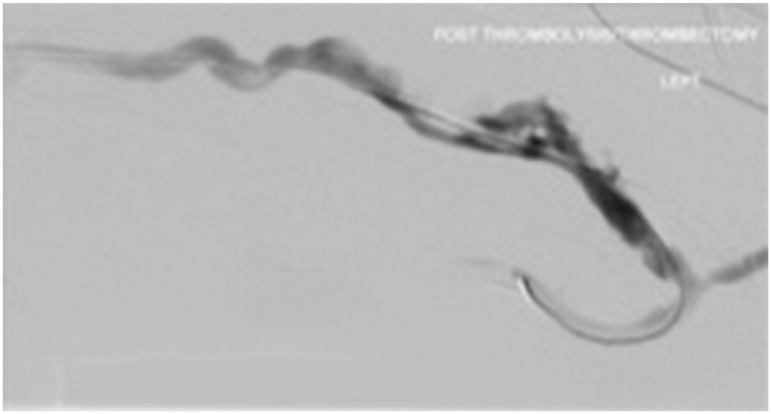

The procedure was performed according to our previously described centre protocol.13,14) Briefly, antegrade and retrograde vascular sheaths/cannulae were placed in the thrombosed AVG/AVF under ultrasound guidance. The thrombolytic agent choices and doses were at the operator’s discretion. Via the sheaths/cannulae, 2–6 mg of recombinant tissue plasminogen activator (r-TPA) was instilled directly into the thrombosed segment of the access. When the operator chose urokinase, the occlusions were crossed with a glide wire and angiographic catheter antegradely. A central venogram was performed, followed by a pullback venogram. Urokinase diluted in 10,000 unit/mL concentration was then administered along with the thrombus via the angiographic catheter or thrombolytic catheter. Balloon angioplasty was then performed to treat the underlying culprit stenosis and macerate the clot. The arterial inflow was swept to clear the arterial plug at the arteriovenous or arterio-graft anastomosis using a 5.5Fr over-the-wire Fogarty balloon (Fig. 1). In the presence of residual thrombus, the Cleaner XT™ device was used for mechanical thrombectomy (Fig. 2). The device was introduced as many times as required to clear the residual clot (usually 2–3 times depending on the clot burden and adherence). The culprit stenotic lesions were either dilated with high-pressure balloons or stented, depending on recoil/dissection and location of the culprit lesions. Completion angiography was then performed to document flow restoration (Fig. 3).

Fig. 3 The appearance of an aneurysmal segment of arteriovenous fistula after applying Cleaner XT™.